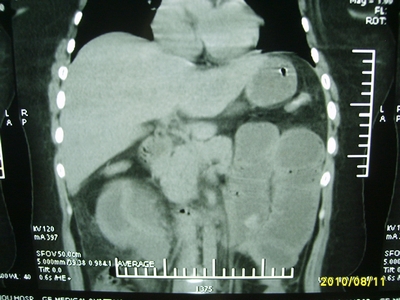

5天前突发腹痛剧烈难忍,伴解淡血水样便。近一天来腹痛缓解,没有明显的腹膜炎的体征。今天照的腹部ct。从ct上看感觉是一个绞窄性肠梗阻,但是现在没有腹痛。不好解释

请放射科的专家,帮帮看看。从影像学的角度来看看。这是不是一个绞窄性肠梗阻。

要有麻烦了,感觉小肠有套叠还有扭转改变,估计部分已有坏死。

高位肠梗阻(不全性),原因小肠(空肠)扭转,肠壁水肿增厚,成年人肠梗阻要排除合并占位,建议手术。

绞窄性肠梗阻_肠管套叠 扭转,肠壁明显水肿。

病人现在没有腹痛。怪了。从影像上来看。确实是绞窄了。但是没有腹痛。没有明显的腹膜炎的体征。确实有不好解释。难道是坏死了。反而不痛了。怪怪怪

支持绞窄性肠梗阻,肠壁明显水肿并见有多发小泡状积气--肠坏死

考虑绞窄性肠梗阻并肠坏死。